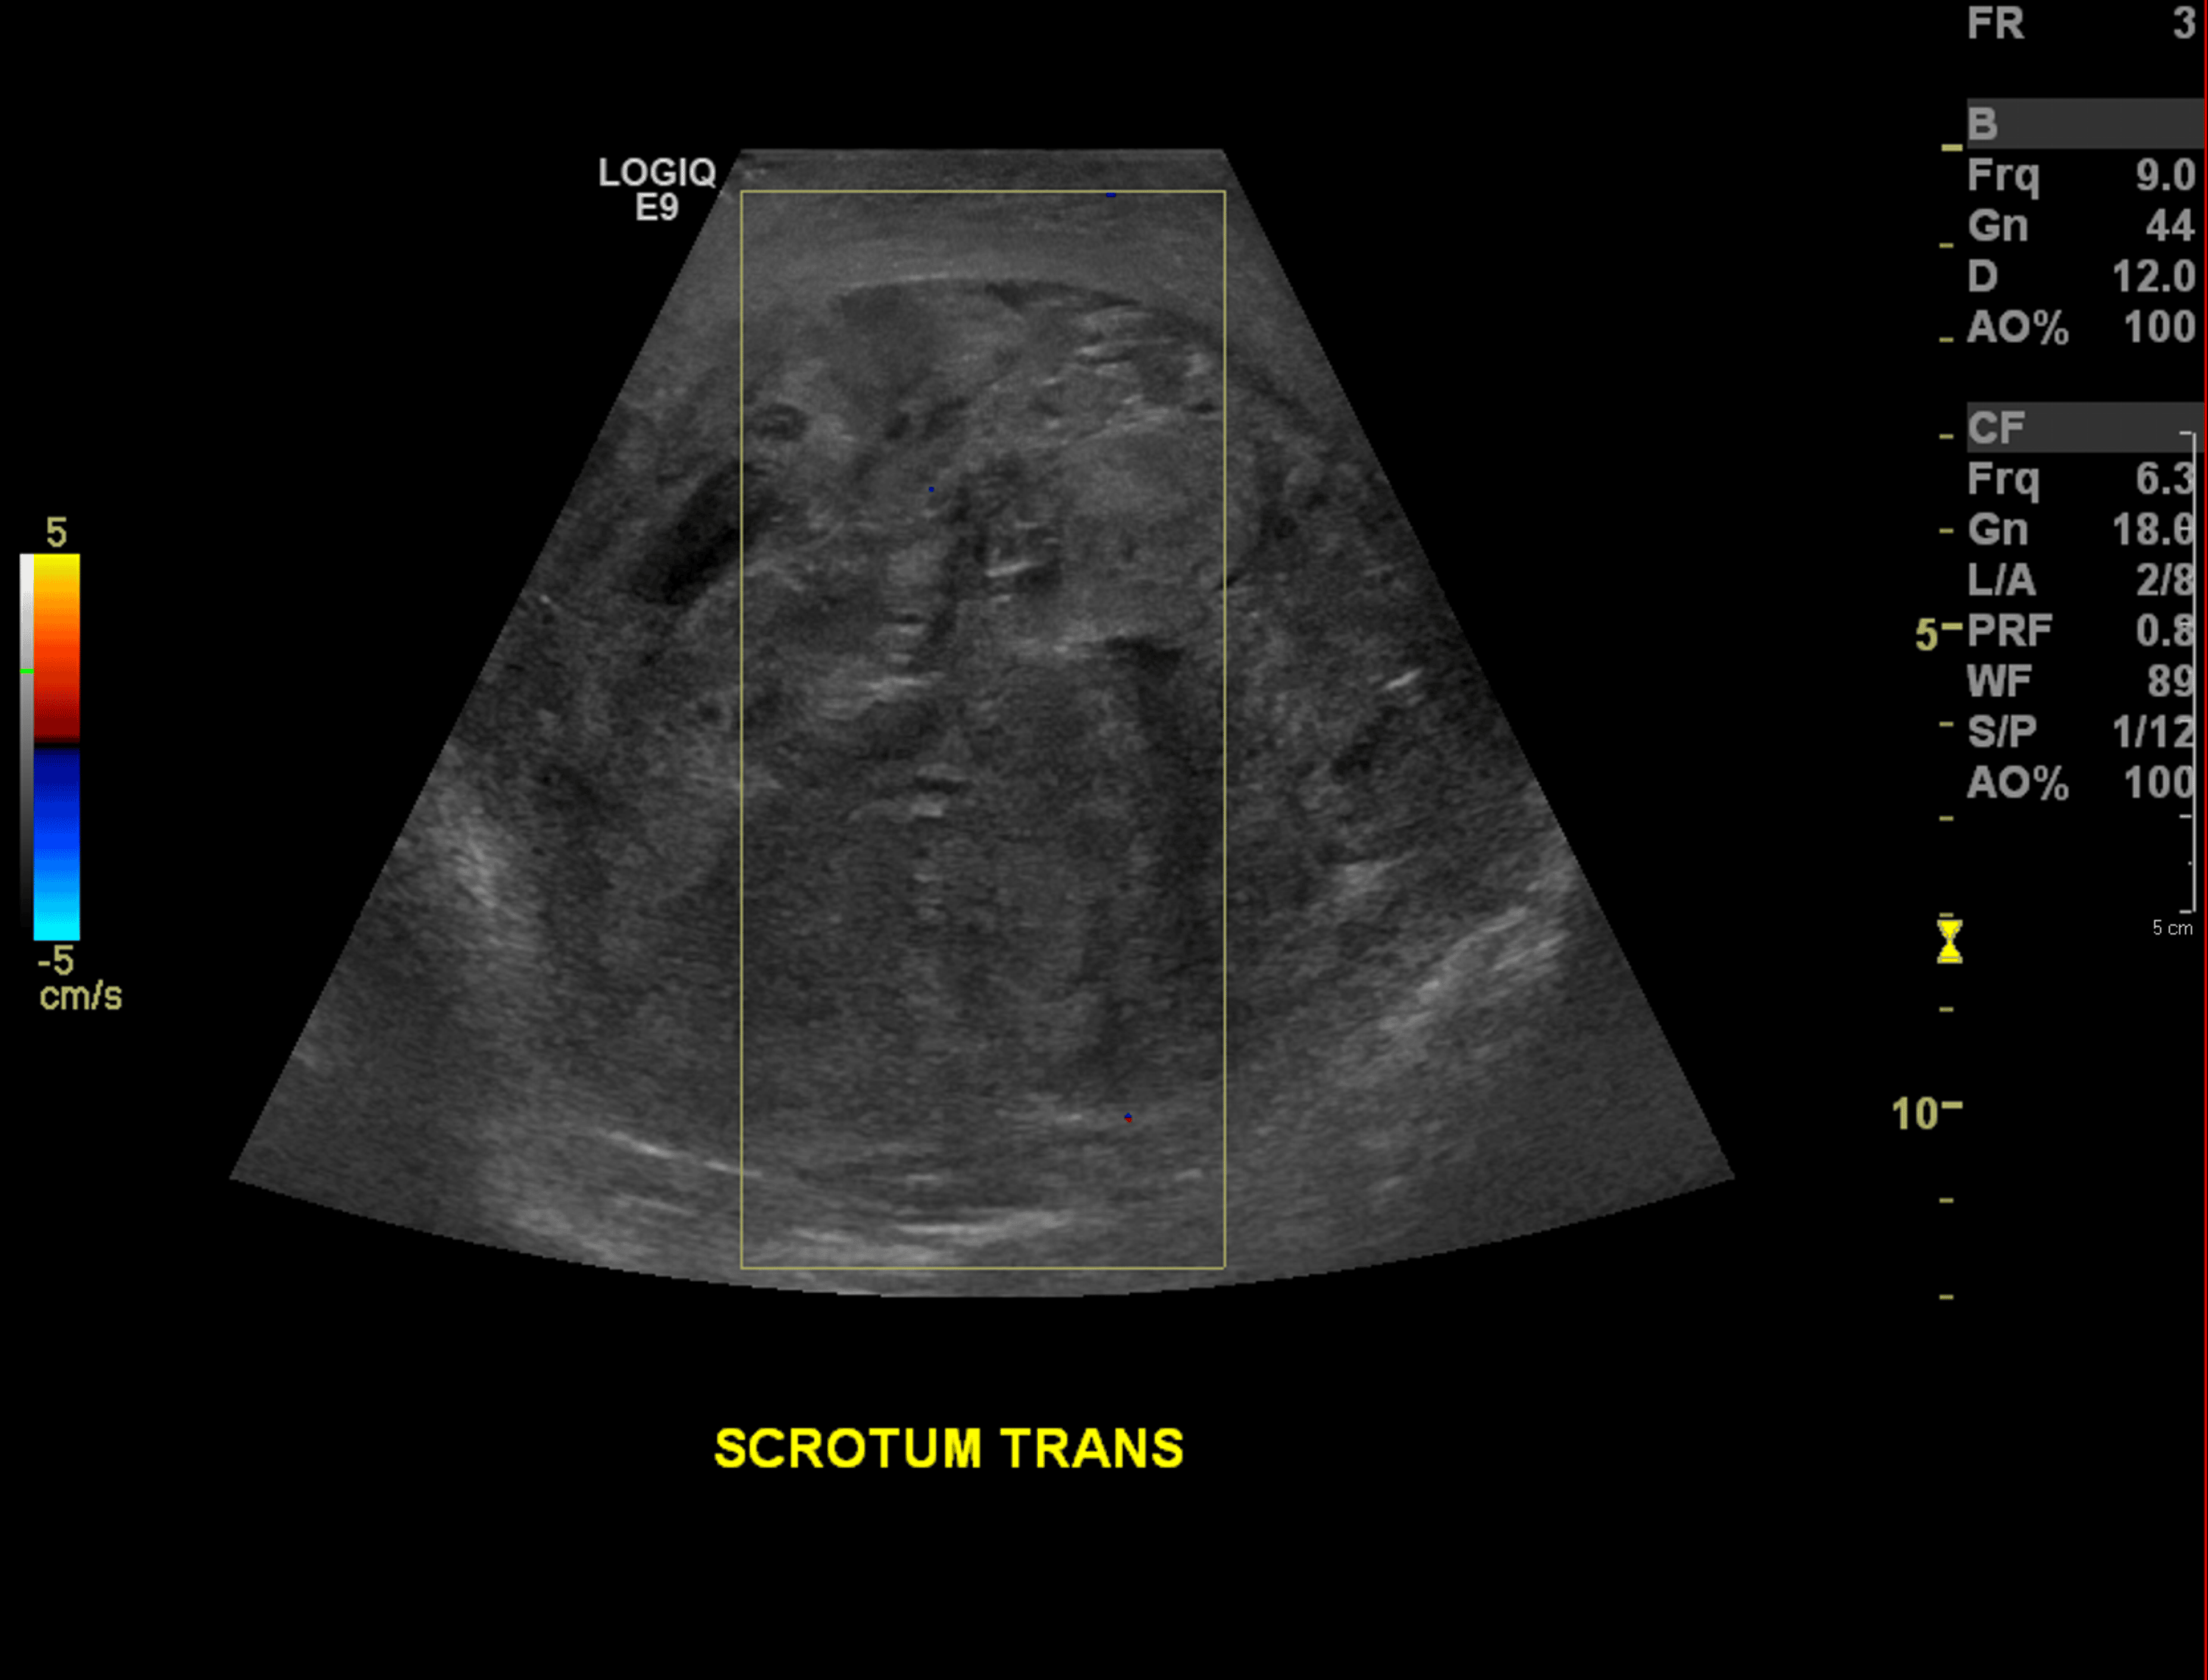

Cureus A Rare Case of Postorchidectomy Arterial Injury With Rapidly Enlarging Scrotal

Cureus A Rare Case of Postorchidectomy Arterial Injury With Rapidly Enlarging Scrotal Coil Embolization Scrotum  During the procedure the doctor makes a small nick in the skin, (usually in the groin). Varicocele embolization is a type of medical procedure. Varicocele embolization is a minimally invasive procedure which is used to treat abnormal enlargement and dysfunctional veins which. It redirects blood away from an enlarged vein in your scrotum. Varicocele embolization is an outpatient procedure with. Coil Embolization Scrotum.

Cureus A Rare Case of Postorchidectomy Arterial Injury With Rapidly Enlarging Scrotal Coil Embolization Scrotum  It redirects blood away from an enlarged vein in your scrotum. During the procedure the doctor makes a small nick in the skin, (usually in the groin). Coils are commonly used embolic for varicocele, and both detachable and pushable. It redirects blood away from an enlarged vein in your scrotum. There are several options for the treatment of varicocele, including. Coil Embolization Scrotum.

Cureus A Rare Case of Postorchidectomy Arterial Injury With Rapidly Enlarging Scrotal Coil Embolization Scrotum  Varicocele embolization is a type of medical procedure. It redirects blood away from an enlarged vein in your scrotum. Varicocele embolization is an outpatient procedure with a short recovery time. Coils are commonly used embolic for varicocele, and both detachable and pushable. It redirects blood away from an enlarged vein in your scrotum. During the procedure the doctor makes a. Coil Embolization Scrotum.

Cureus A Rare Case of Postorchidectomy Arterial Injury With Rapidly Enlarging Scrotal Coil Embolization Scrotum  During the procedure the doctor makes a small nick in the skin, (usually in the groin). Varicocele embolization is a type of medical procedure. It redirects blood away from an enlarged vein in your scrotum. Varicocele embolization is a minimally invasive procedure which is used to treat abnormal enlargement and dysfunctional veins which. There are several options for the treatment. Coil Embolization Scrotum.

Cureus A Rare Case of Postorchidectomy Arterial Injury With Rapidly Enlarging Scrotal Coil Embolization Scrotum  Varicocele embolization is a minimally invasive procedure which is used to treat abnormal enlargement and dysfunctional veins which. Coils are commonly used embolic for varicocele, and both detachable and pushable. There are several options for the treatment of varicocele, including surgical repair either by open or microsurgical approach, laparoscopy, or. During the procedure the doctor makes a small nick in. Coil Embolization Scrotum.

Cureus A Rare Case of Postorchidectomy Arterial Injury With Rapidly Enlarging Scrotal Coil Embolization Scrotum  Varicocele embolization is an outpatient procedure with a short recovery time. Coils are commonly used embolic for varicocele, and both detachable and pushable. There are several options for the treatment of varicocele, including surgical repair either by open or microsurgical approach, laparoscopy, or. During the procedure the doctor makes a small nick in the skin, (usually in the groin). It. Coil Embolization Scrotum.